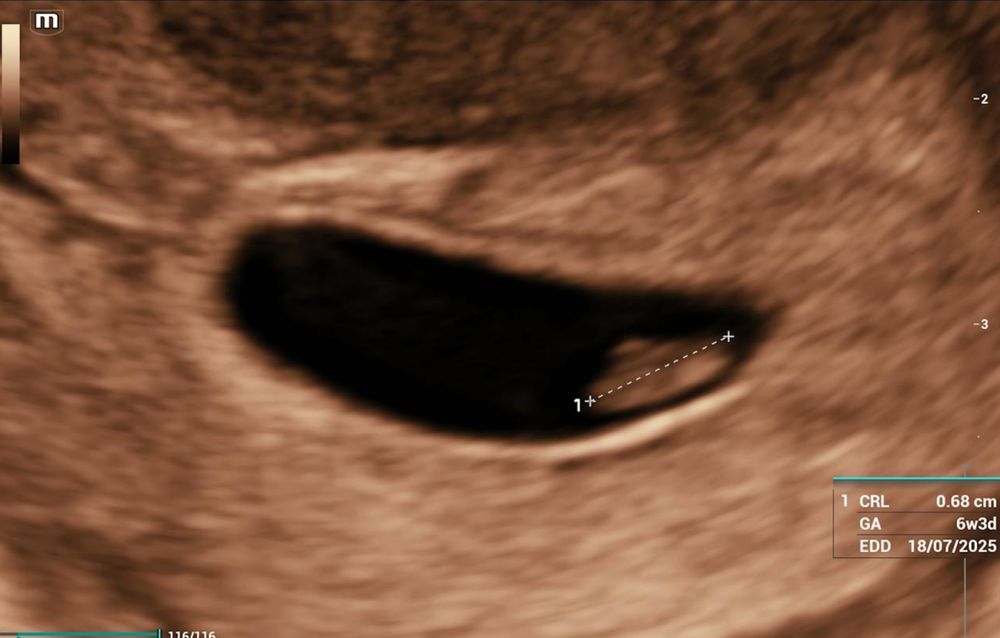

Была сегодня на первом узи, по месячным 7+2, по овуляции должно быть 7+0 или 7+1 (отслеживала тестами и по ощущениям), первый призрак увидела на примерно 9 дпо.

ктр 0,68мм что аппарат считал как 6+3, но это невозможно так как не могла же я получить положительный тест на 3-4дпо. Второе фото - желточный мешок. Ни ЖМ ни ПЯ не измерили.

Сб+, на этом сроке у нас не считают частоту, только смотрят мерцание. Мне показалось достаточно медленное, но врач сказала что хорошее и ритмичное.

Но непонятно сформулировала - в целом хорошее, или для 6+3 хорошее.